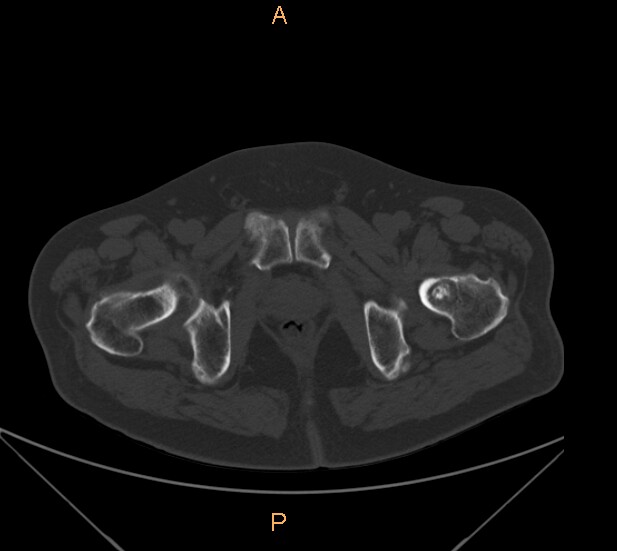

标题: CT29088:左股骨颈 [打印本页]

标题: CT29088:左股骨颈

左侧股骨颈疼痛。

左股骨颈软骨瘤可能,建议增强或mri

内生软骨瘤。

不排除骨样骨瘤

不排除左侧股骨颈内生软骨瘤可能。

内生软骨瘤年龄较小,分叶状,局部皮质有改变,钙化为环形半环形,没有这么粗大。

左股骨颈软骨瘤可能,建议增强或mri  。